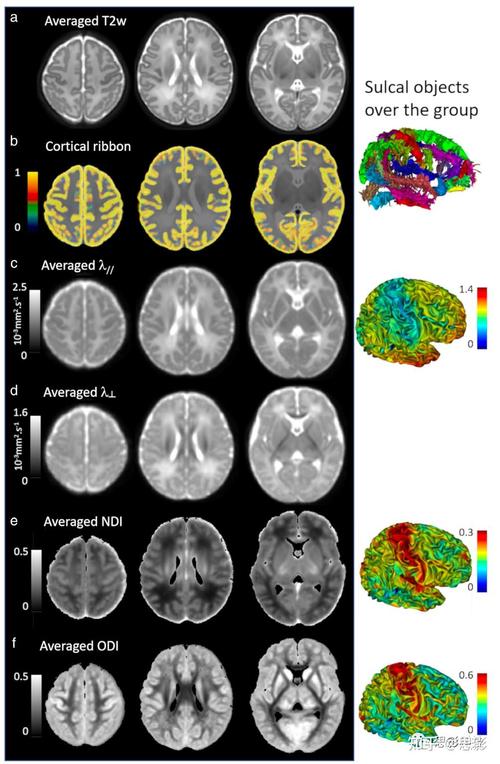

(一)中枢神经系统:MRI最核心的战场

大脑是新生儿最需要精密评估的器官之一,MRI在以下情况中扮演着不可替代的角色:

(图片来源网络,侵删)- 检查什么: 这是新生儿期最常见的脑部问题之一,通常由围产期窒息引起,MRI可以精确评估脑损伤的部位、范围和严重程度,例如是皮层、基底节还是脑干受累,这对于判断宝宝未来的神经发育预后(如是否可能出现脑瘫、癫痫、智力障碍等)至关重要,并指导后续的康复治疗。

- 检查什么: 检测脑结构是否正常发育。

- 脑白质质: 评估髓鞘化进程是否正常。